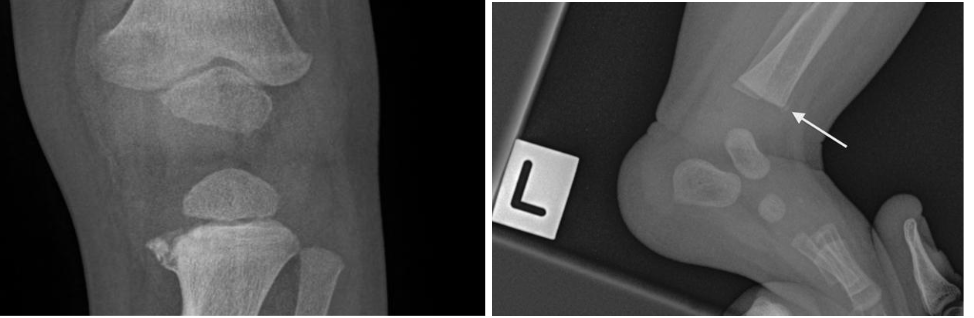

Metaphyseal Fractures

These are also known as bucket handle/corner fractures. These are the most SPECIFIC and PATHOGNOMONIC for nonaccidental trauma. This type of injury often occurs as microfractures from whiplash/shearing forces. This often presents exclusively in children under 2 years old because they are small enough to be shaken and not enough muscle development has occurred to protect their own limbs. However, please check patient’s birth history! In newborns, this can be a finding that can occur after traumatic deliveries where the baby presents in the breech position.